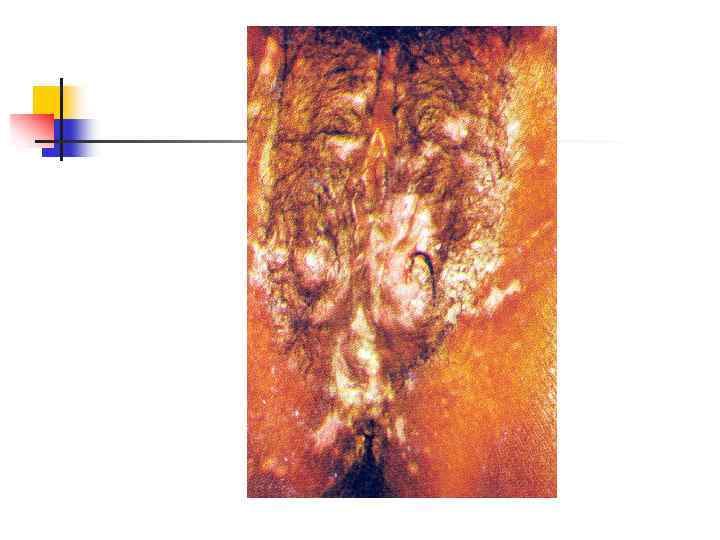

Герпес половых органов: первичная инфекция Множественные эрозии на вульве и коже промежности. Эрозии чрезвычайно болезненны, многие из них сливаются между собой. Увеличены паховые лимфоузлы, мочеиспускание причиняет жгучую боль

Герпес половых органов: первичная инфекция Множественные эрозии на вульве и коже промежности. Эрозии чрезвычайно болезненны, многие из них сливаются между собой. Увеличены паховые лимфоузлы, мочеиспускание причиняет жгучую боль